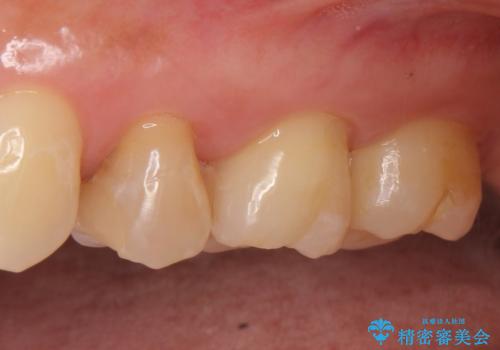

左上5は再根管治療を行い症状の緩解を確認後、オールセラミッククラウンによる補綴を行いました。

左上6、7番目の歯もしみるとのことだったので古い樹脂及び虫歯を除去後、オールセラミッククラウンによる補綴を行いました。

今回用いたオールセラミッククラウンはジルコニアフレームという白い素材の上にセラミックを盛っているため、審美性が非常に高いのが特徴です。

また、ジルコニアは人工ダイヤモンドの材料にも使われているほど高い強度を持っており、そのためオールセラミッククラウンは審美性だけでなく、奥歯やブリッジの補綴も可能とするクラウンです。